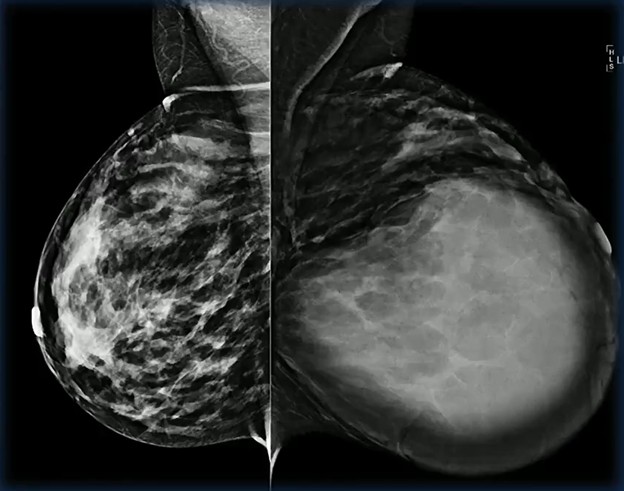

Lactating adenomas are the second-most common mass encountered in pregnant and lactating patients. Imaging characteristics often mirror fibroadenomas and can be indistinguishable on both mammography and ultrasound. Therefore, definitive diagnosis typically depends on histology, rather than imaging alone.

Solid Target: Physiologic lactational changes can introduce cystic elements, creating mixed solid–cystic morphology. When biopsy is indicated, precision matters: sampling the solid portion is essential to secure an accurate diagnosis and avoid false reassurance…as in the case of this 36-year-old postpartum patient (lump x 3 months) with biopsy-proved lactating adenoma.